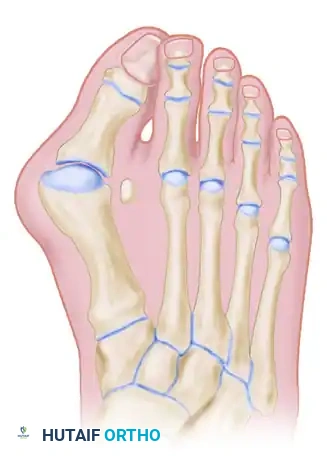

The classic "rheumatoid foot" presents with severe hallux valgus, dorsal subluxation or frank dislocation of the lesser metatarsophalangeal (MTP) joints, claw toes, hammer toes, and the formation of painful adventitial bursae. As the proximal phalanges subluxate dorsally, the plantar metatarsal fat pad is drawn distally, leaving the prominent metatarsal heads directly exposed to plantar pressure, leading to intractable plantar keratoses and ulceration.

Forefoot arthroplasty is directed primarily at the severe metatarsophalangeal joint deformities. The overarching goals are to relieve pain, correct deformity, improve cosmesis, enhance ambulatory function, and allow the patient to wear a reasonable variety of footwear.

Regardless of the specific surgical approach (plantar vs. dorsal incisions), adequate bony resection is mandatory. The phalanges must be allowed to realign loosely with the metatarsal remnants without any soft tissue tension. Insufficient relaxation of the soft tissues around the MTP joints due to inadequate bone resection will severely compromise the result, leading to recurrent dorsal subluxation and stiffness.

The Metatarsal Cascade

When performing a resection arthroplasty, the surgeon must carefully contour the remaining metatarsal necks. Unequal lengths of the metatarsal remnants, or metatarsals that do not cascade in a gentle, parabolic curve from metatarsals two through five, will result in transfer metatarsalgia and a compromised outcome. Furthermore, any bony fragments left in the forefoot weight-bearing pad will act as symptomatic pebbles, causing severe localized pain.